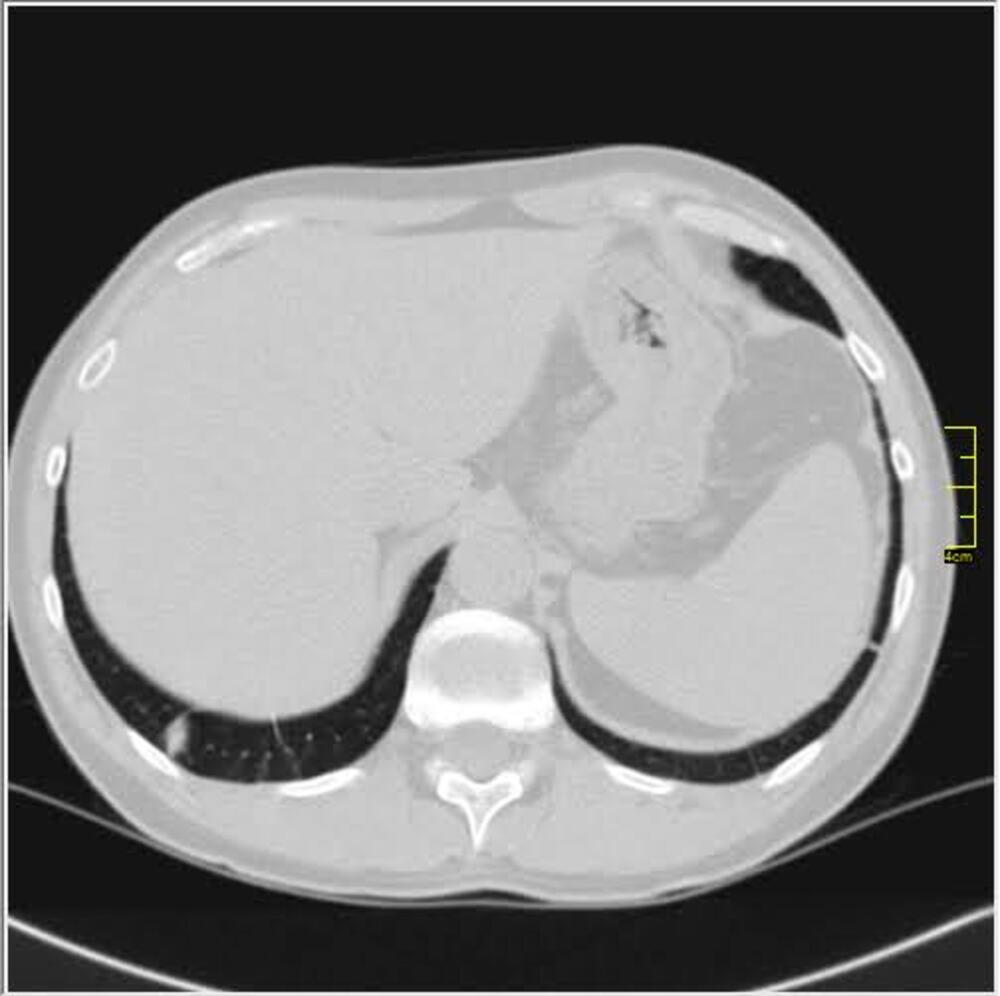

Decembar i januar je dominirao britanski soj. Kada se pogledaju njegove slike vidi se razlika u odnosu na divlji a blizu je onoga koji je bio u leto 2020. godine.

Decembar, januar, februar, mart. 2020/21.

Gustina promena je različita, razlikovala se i klinička slika. retko u decembru ali do marta skoro isključiv.